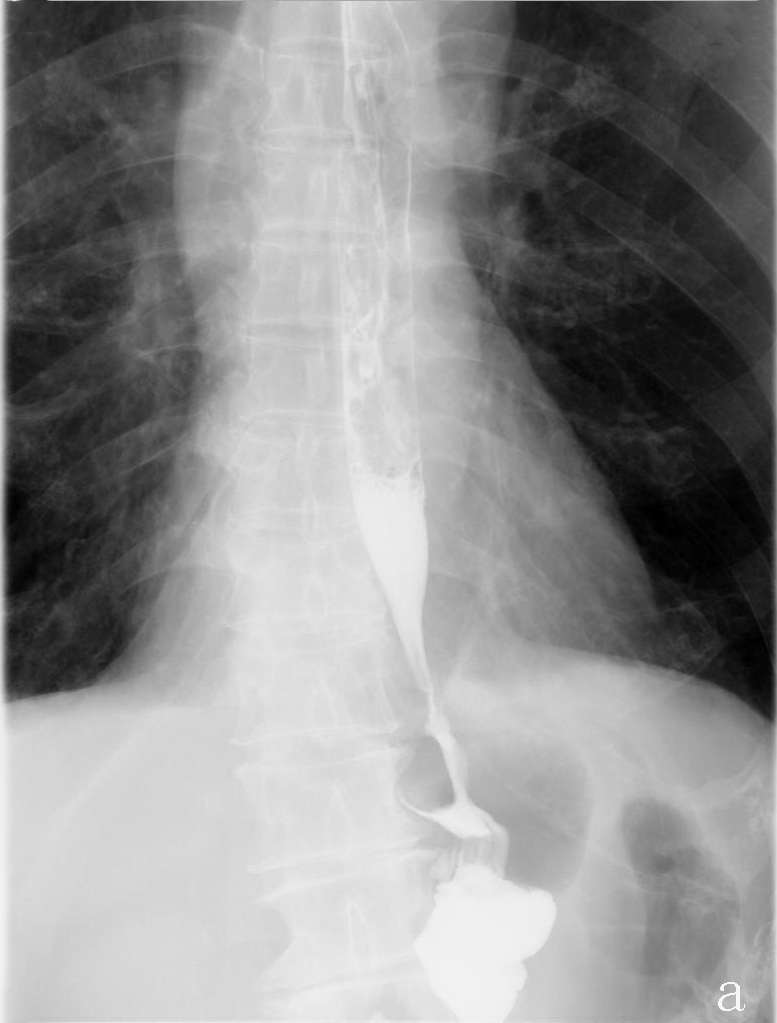

The average duration of surgery was 277.5 min and average intraoperation blood loss was 100 ml. The postoperative exhaust time was 3 days in both cases. Upper digestive tract water-soluble angiography was performed on the 6th postoperative day to rule out anastomotic leakage and anastomotic stenosis (Figure 3), oral feeding was resumed, and the nutrient tube was removed. Liquid diet was followed for 7 days and patients were discharged from the hospital on the 8th day after operation. Average of 19 lymph nodes were dissected.

Figure 3:Upper digestive tract water-soluble angiography.